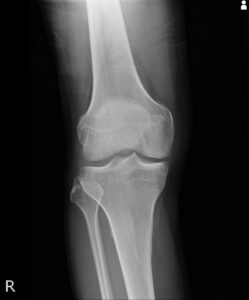

変形性膝関節症は、膝関節の軟骨がすり減ることで関節が変形し、痛みや動きの制限を引き起こす疾患です。特に中高年の方に多く見られ、進行すると日常生活にも大きな支障が出てきます。原因は、加齢、体重、過去の怪我などです。

主な症状として、「動き始め」や「立ちしゃがみ」、「歩行や階段昇降時」といった荷重がかかるタイミングでの痛みが挙げられます。また、「膝に水がたまる」「関節の変形(O脚・X脚)が目立つ」「膝の曲げ伸ばしが制限される」といった所見も、変形性膝関節症の特徴です。